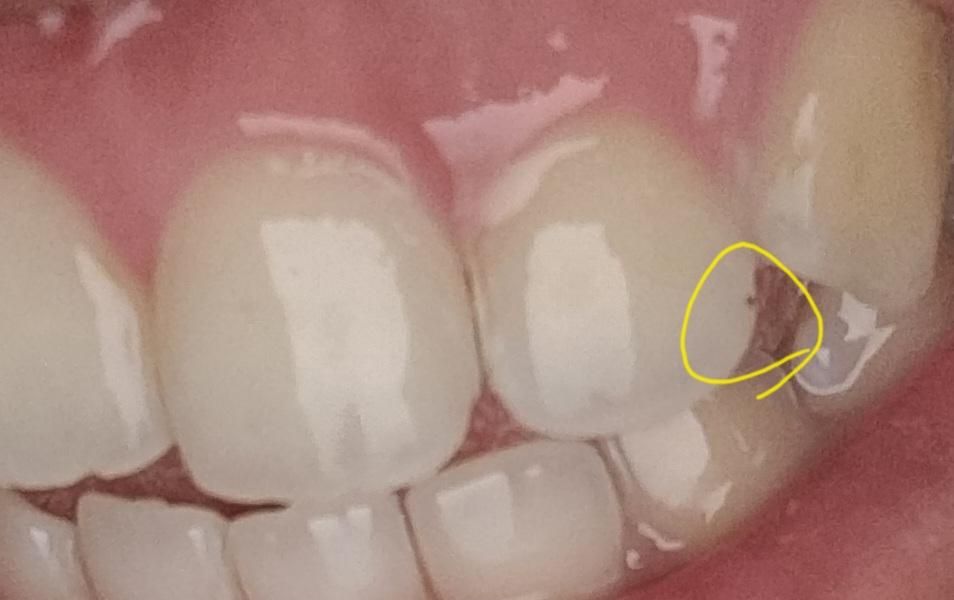

이게 언제 생긴건진 모르겠는데 작년에 발견했고 그때랑 크기는 비슷해요 치과에서는 변색 같다고는 하는데 구석에 있어서 잘 보이지는 않지만 계속보다보니 신경이 쓰여요..

네 저 부위는 충치가 잘 생기지 않는 곳이기 때문에 변색이 맞을 것입니다. 변색차제로 치아건강에 큰 영향이 있지는 않지만, 저렇게 점처럼 한군데만 콕하고 있는 변색은 아마 그 부분에 작게 옴폭한 홈이 있을 것입니다. 홈이 없어야 할 곳에 홈이 있으면 이물질 및 세균이 달라붙기 비교적 쉽고 추후 충치가 생길 가능성도 있기에 홈자체를 없애주시는게 좋은 경우도 있습니다. 작년부터 있었다면 칫솔질로는 제거가 어려울 것 같고, 치과 가셔서 제거해달라고 하시면 치과에서 할 수 있는 여러가지 방법 중 알맞은 것을 사용해 없애주실겁니다. 홈의 깊이가 얕다면 아예 그 부분을 매끄럽게 다듬어버리면 착색도 같이 사라질 수있구요. 아니면 착색만 제거하고 레진으로 덮을 수도 있구요.

사진으로 봤을 경우에는 단순한 착색일 수도 있지만 충치일 수도 있습니다. 착색이라면 간단하게 제거할 수 있으며 충치라면 치료를 해주는 것이 좋을 수 있습니다.

자세한 확인을 위해서 치과에서 진료를 받아보는 것을 권유드립니다.

변색인지 충치 인지 확실하지 않지만 치과에서 드릴로 긁어 보면 확인 가능합니다. 긁어서 없어지면 변색 또는 착색이며, 긁어도 안쪽까지 깊다면 충치입니다.

네 해당 부위는 충치가 생길만한 위치도 아니고 충치의 양상도 아닌 것 같습니다. 변색이나 착색으로 보입니다. 계속 신경쓰인다면 해당 부위 파내고 레진 등 치아색 나는 재료로 메꿔줄 수 있습니다.